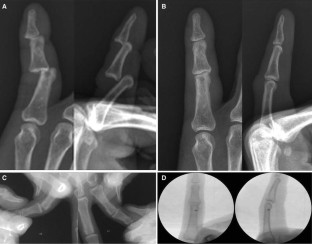

Simultaneous double dislocation of the interphalangeal joint in a finger

Isolated traumatic dislocation of the distal and proximal interphalangeal joints of the fingers is a common occurrence. However, simultaneous dislocation of both interphalangeal joints in a single finger appears to be a rare event. We report five cases of simultaneous dislocation of both interphalangeal joints in a single finger with a review of the literature.

Fig. 1